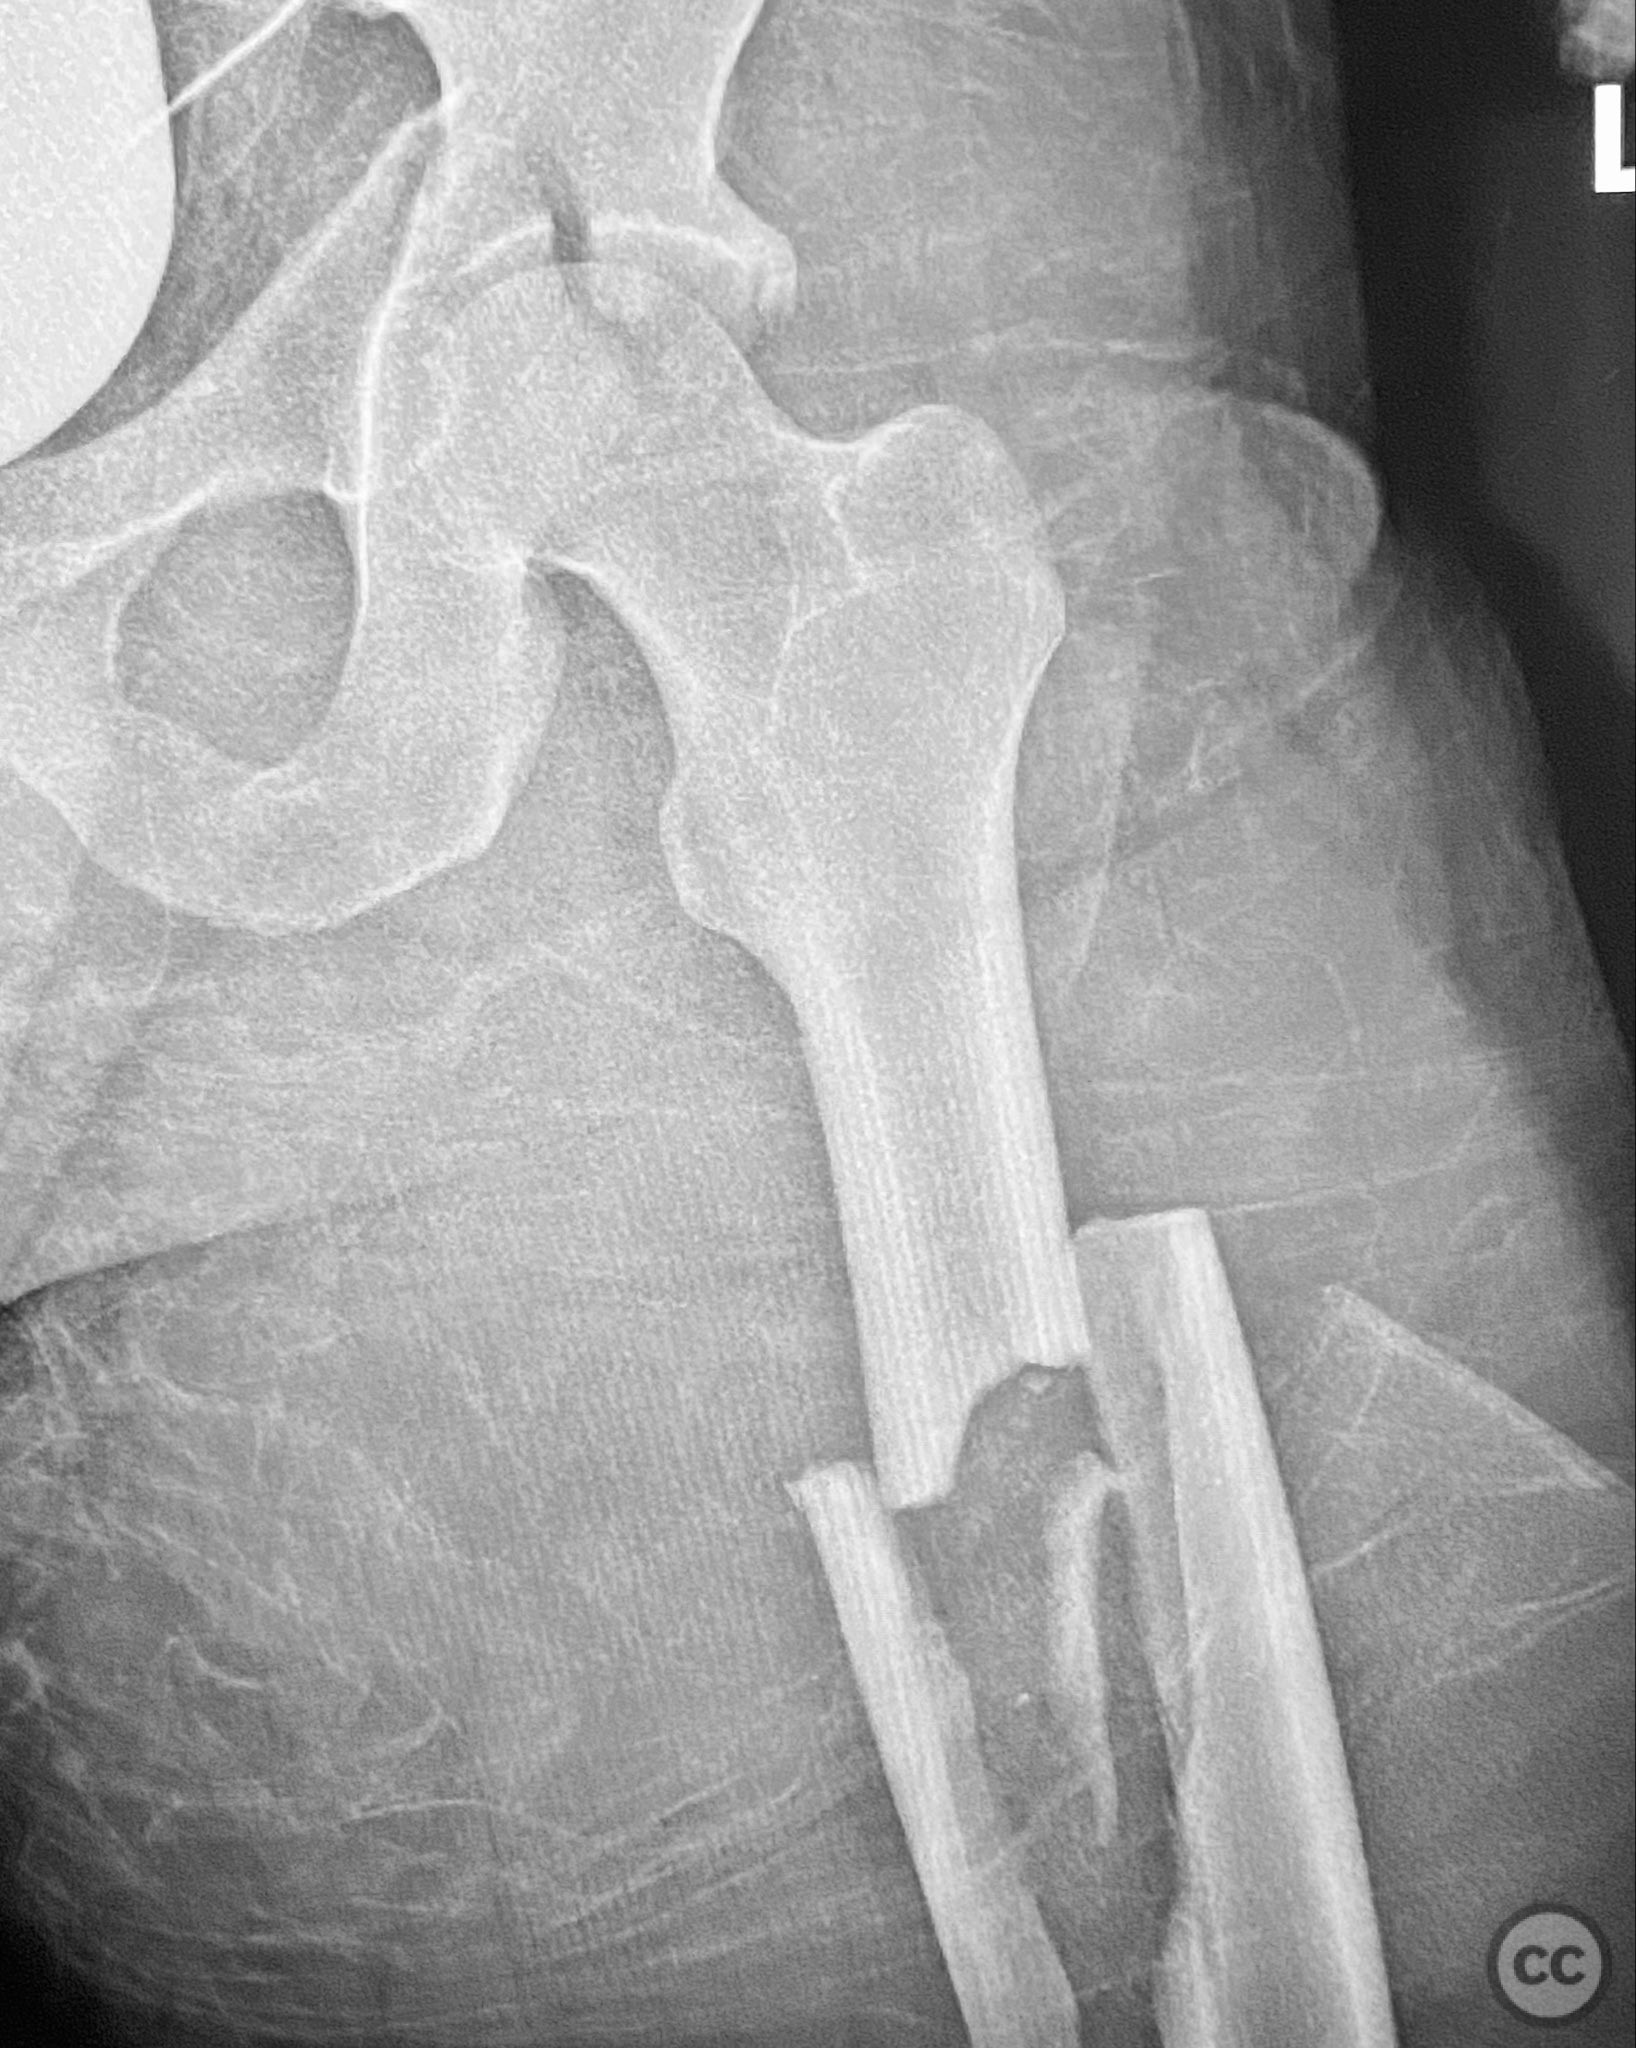

Clinical and radiological findings:  Adult male with a closed, comminuted left femoral shaft fracture and complex pelvic ring injury. Initial imaging demonstrated bilateral sacroiliac (SI) joint disruptions and a left-sided transtectal transverse acetabular fracture (Letournel-Judet: transverse type), with the fracture line exiting through the posterior wall region but without a discrete posterior wall fragment. The femoral head was displaced caudally, following the unstable distal acetabular segment, resulting in loss of congruency with the intact acetabular dome. There was also a symphyseal disruption. No associated abdominal, visceral, thoracic, cranial, or other injuries were present. Application of a circumferential pelvic binder resulted in visible changes in pelvic alignment on imaging. AO/OTA Classification: - Pelvic ring: 61-C1.3 (bilateral SI joint disruption, complete instability) - Acetabulum: 62-B1 (transverse fracture) - Femur: 32-C3 (comminuted diaphyseal fracture)

Planning remarks:  The preoperative plan involved staged management: initial resuscitation and provisional stabilization with a circumferential pelvic binder, followed by operative reduction and fixation of the pelvic ring using an anterior two-pin external fixator for SI joint compression and reduction, percutaneous iliosacral (IS) and transsacral (TS) screw fixation, and subsequent intramedullary nailing of the femur. Definitive acetabular fixation was planned via a posterior Kocher-Langenbeck approach in the prone position.

Orthopaedic implants used:   - Anterior two-pin external fixator - Percutaneous iliosacral screw(s) - Percutaneous transsacral screw(s) - Intramedullary femoral nail - 4.5 mm cortical screws (acetabular fixation) - Posterior column reconstruction plate(s)